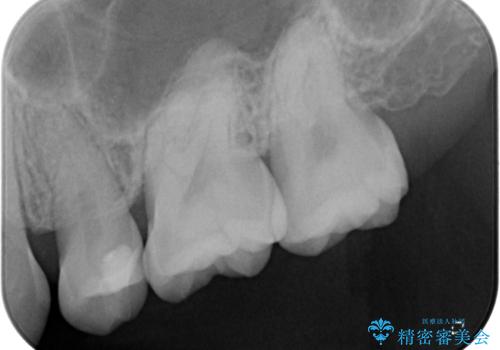

- 食事の度に物が挟まるとのことで来院された患者様です。

目視でも欠損が認められ、レントゲン写真からもむし歯が認められる状態でした。

患者様と相談の上、セラミックインレーで精密な修復治療を行うこととしました。

精密な型取りと、ラバーダム防湿下での接着操作により、歯と詰め物の隙間を最小限にとどめることができ、良好な長期予後が期待できます。